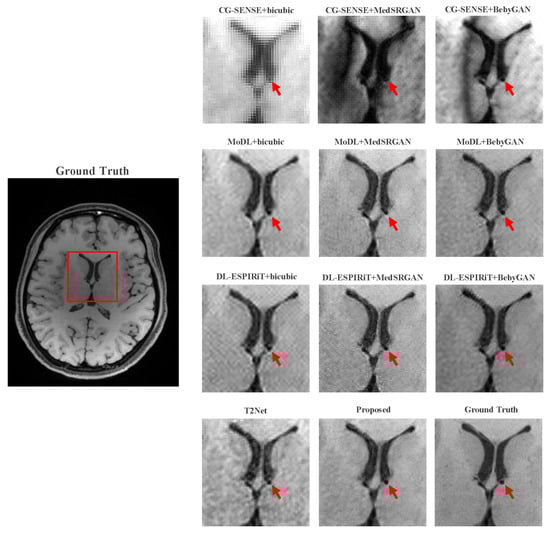

For a more intuitive comparison, we provide visual comparisons for each method. In Figure 5 and Figure 6, we illustrate the axial and sagittal views of the 2D brain dataset, respectively. In Figure 7 and Figure 8, we display the brain image and neck image of the 3D VWI dataset. For each method, we show the restorations along with the corresponding error maps. The images are placed on the left, the error maps on the right, and the PSNR and LPIPS metrics of each image are shown at the bottom right corner. From the error maps, it is evident that our proposed method consistently produces high-quality results with improved visual fidelity and better retention of structural information compared to the other methods.

Figure 9 and Figure 10 present the zoomed-in images of the enclosed parts in the ground truth. Our proposed method can faithfully recover the fine structures, as indicated by the red arrows, and successfully preserve the image contrast, as pointed out by the yellow arrow. The high-fidelity restoration achieved by our method in these zoomed-in regions further demonstrates its ability to faithfully recover fine details and enhance image quality.

Figure 10. Zoomed-in view of the VWI dataset comparison experiment.

Bioengineering 10 01107 g010